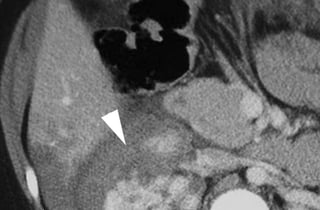

PHOTOS OF CT EVALUATION OF

PREGNANT WOMAN WITH TRAUMA– CT

SCANS DONE AS A PART OF INVESTIGATIONS

DONE IN EMERGENCY --- MATERNAL HEAD

AND ABDOMEN AS PER NEED OF INDIVIDUAL

CASE ---WITHOUT FEAR OF X RAYS

EXPOSURE TO FETUS IN UTERO

PHOTOS OF CTEVALUATION OF PREGNANT WOMAN WITH TRAUMA– CT SCANS DONE AS A PART OF INVESTIGATIONS DONE IN EMERGENCY --- MATERNAL HEAD AND ABDOMEN AS PER NEED OF INDIVIDUAL CASE ---WITHOUT FEAR OF X RAYS EXPOSURE TO FETUS IN UTERO